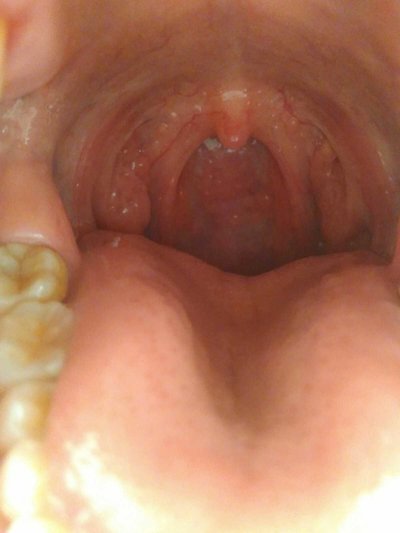

Tongue bite refers to neonatal convulsion, prone to tongue bite, asphyxia, cerebral hypoxia and other complications. Neonatal convulsion is a symptom of the central nervous system dysfunction caused by a variety of reasons (birth injury, hypoxia, metabolic abnormalities, infection and congenital malformations, etc.), which is a sudden abnormal discharge of some neurons in brain tissue, leading to the involuntary contraction of the whole body or local muscles. Which department does tongue bite see? Let's talk about it

See the Department of Stomatology, during the period of tongue injury, we must try not to eat some food containing irritation and spicy, but we can appropriately eat some sweet food, which can restore the tongue injury.